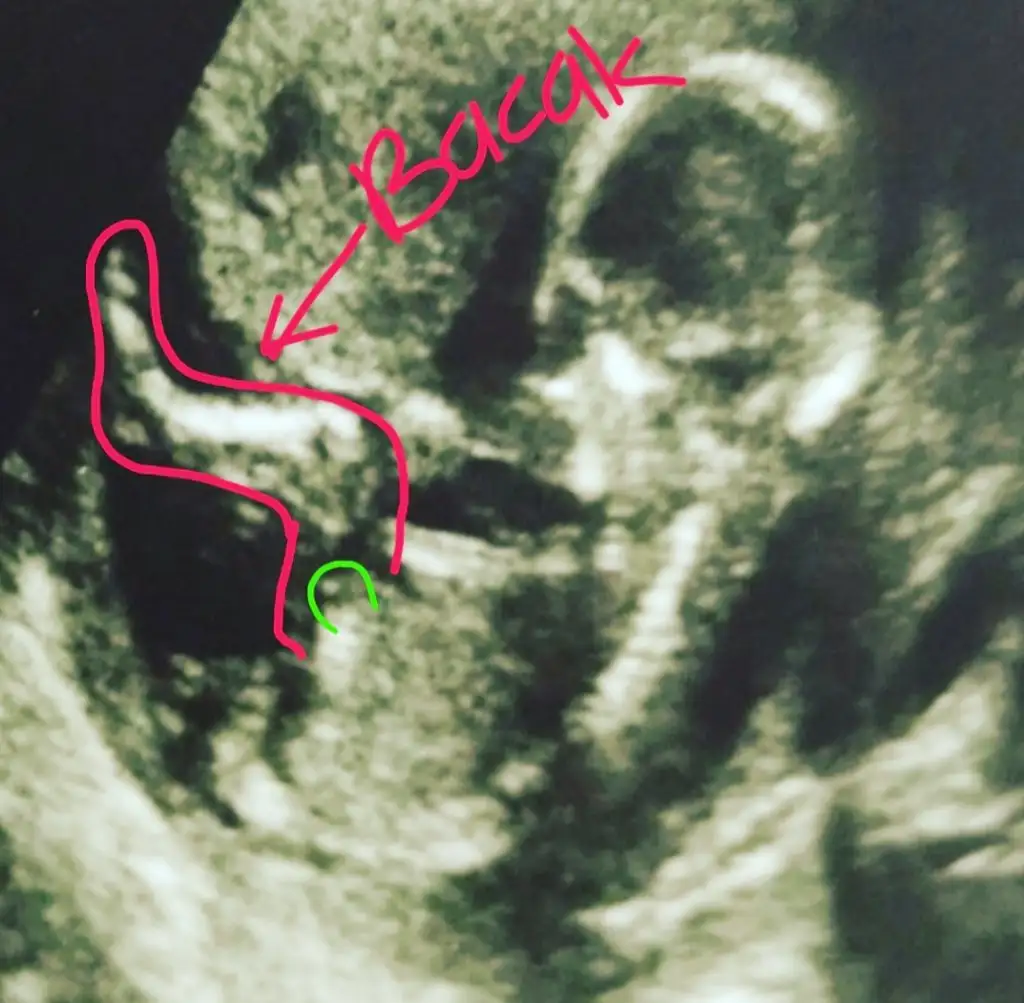

Canım bi de bu var ,ben de bugün başka doktora gittim direkt erkek dedi emin mısınız dedim sanki pipi gördüm dedi ama bir ay sonra netlesir dedi :)

Kız tabiki burda ama sonraki büyük haftada nub olmaz ☺️ demekki kordon gelmiş yoksa diğeri net bariz kız nubu 🙈